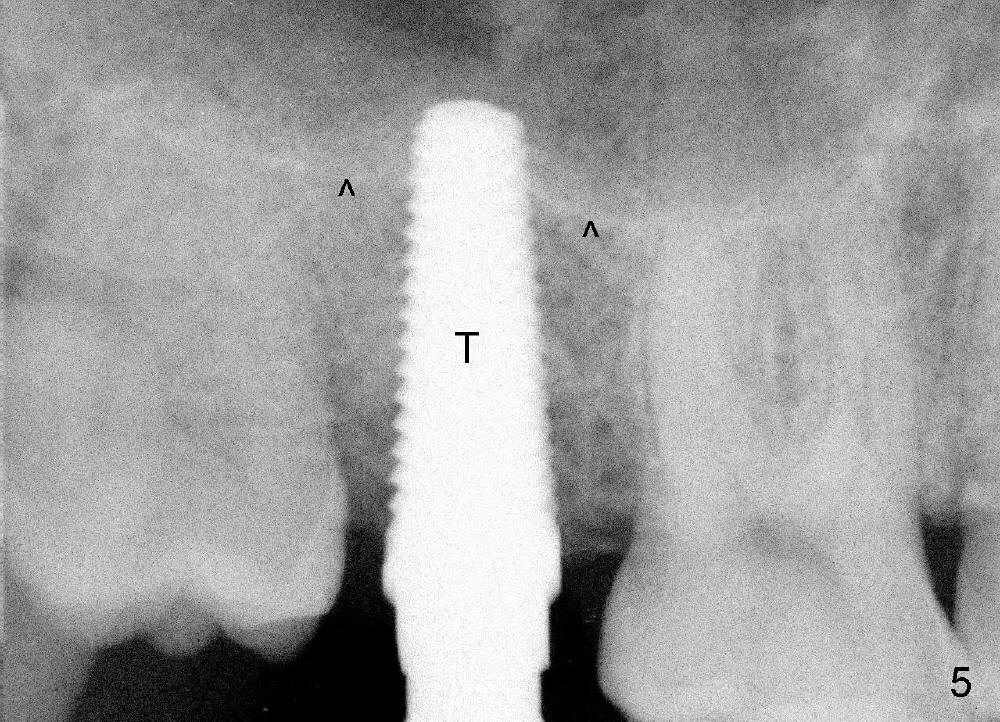

A 42-year-old man is afraid of dentistry. Residual roots of #2 remain untreated for at least 2.5 years (Fig.1). Both the mesiodistal space and the height are limited and unfavorable to restoration (Fig.2,3). Finally he agrees to have treatment, since the tooth #15 is worn so much that it is sensitive to mastication. When the tooth #2 is extracted, the socket is triangular without septum (Fig.4); the bottom of the socket is flat and easy for osteotomy. A 5x17 mm tap has obtained stability once it is placed ~ 14 mm deep (Fig.5). A 5x14 mm implant is placed with insertion torque > 60 Ncm (Fig.6 I), followed by placement of 4x3 mm abutment (A).

To prevent the narrow spaces from getting worse during osteointegration, an immediate provisional is to be fabricated. There is not enough occlusal clearance when the abutment is reduced ~1.5 mm. The abutment is removed; the implant is placed ~ 1 mm deeper with primary stability. Then the occlusal clearance is sufficient; the provisional is made. Mixture of autogenous bone, allograft and Osteogen is placed in the remaining buccal and lingual sockets (Fig.7 *). The provisional is temporarily cemented (Fig.8 P), which keeps the bone graft in place.